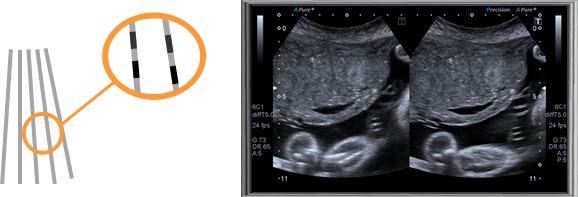

高級復合成像技術 (ApliPure?+)

ApliPure?+ 成像還可以和東芝其他的創新技術共同使用,如精確成像、差量諧波、高級動態血流成像等,為您帶來全新高標準的圖像質量。